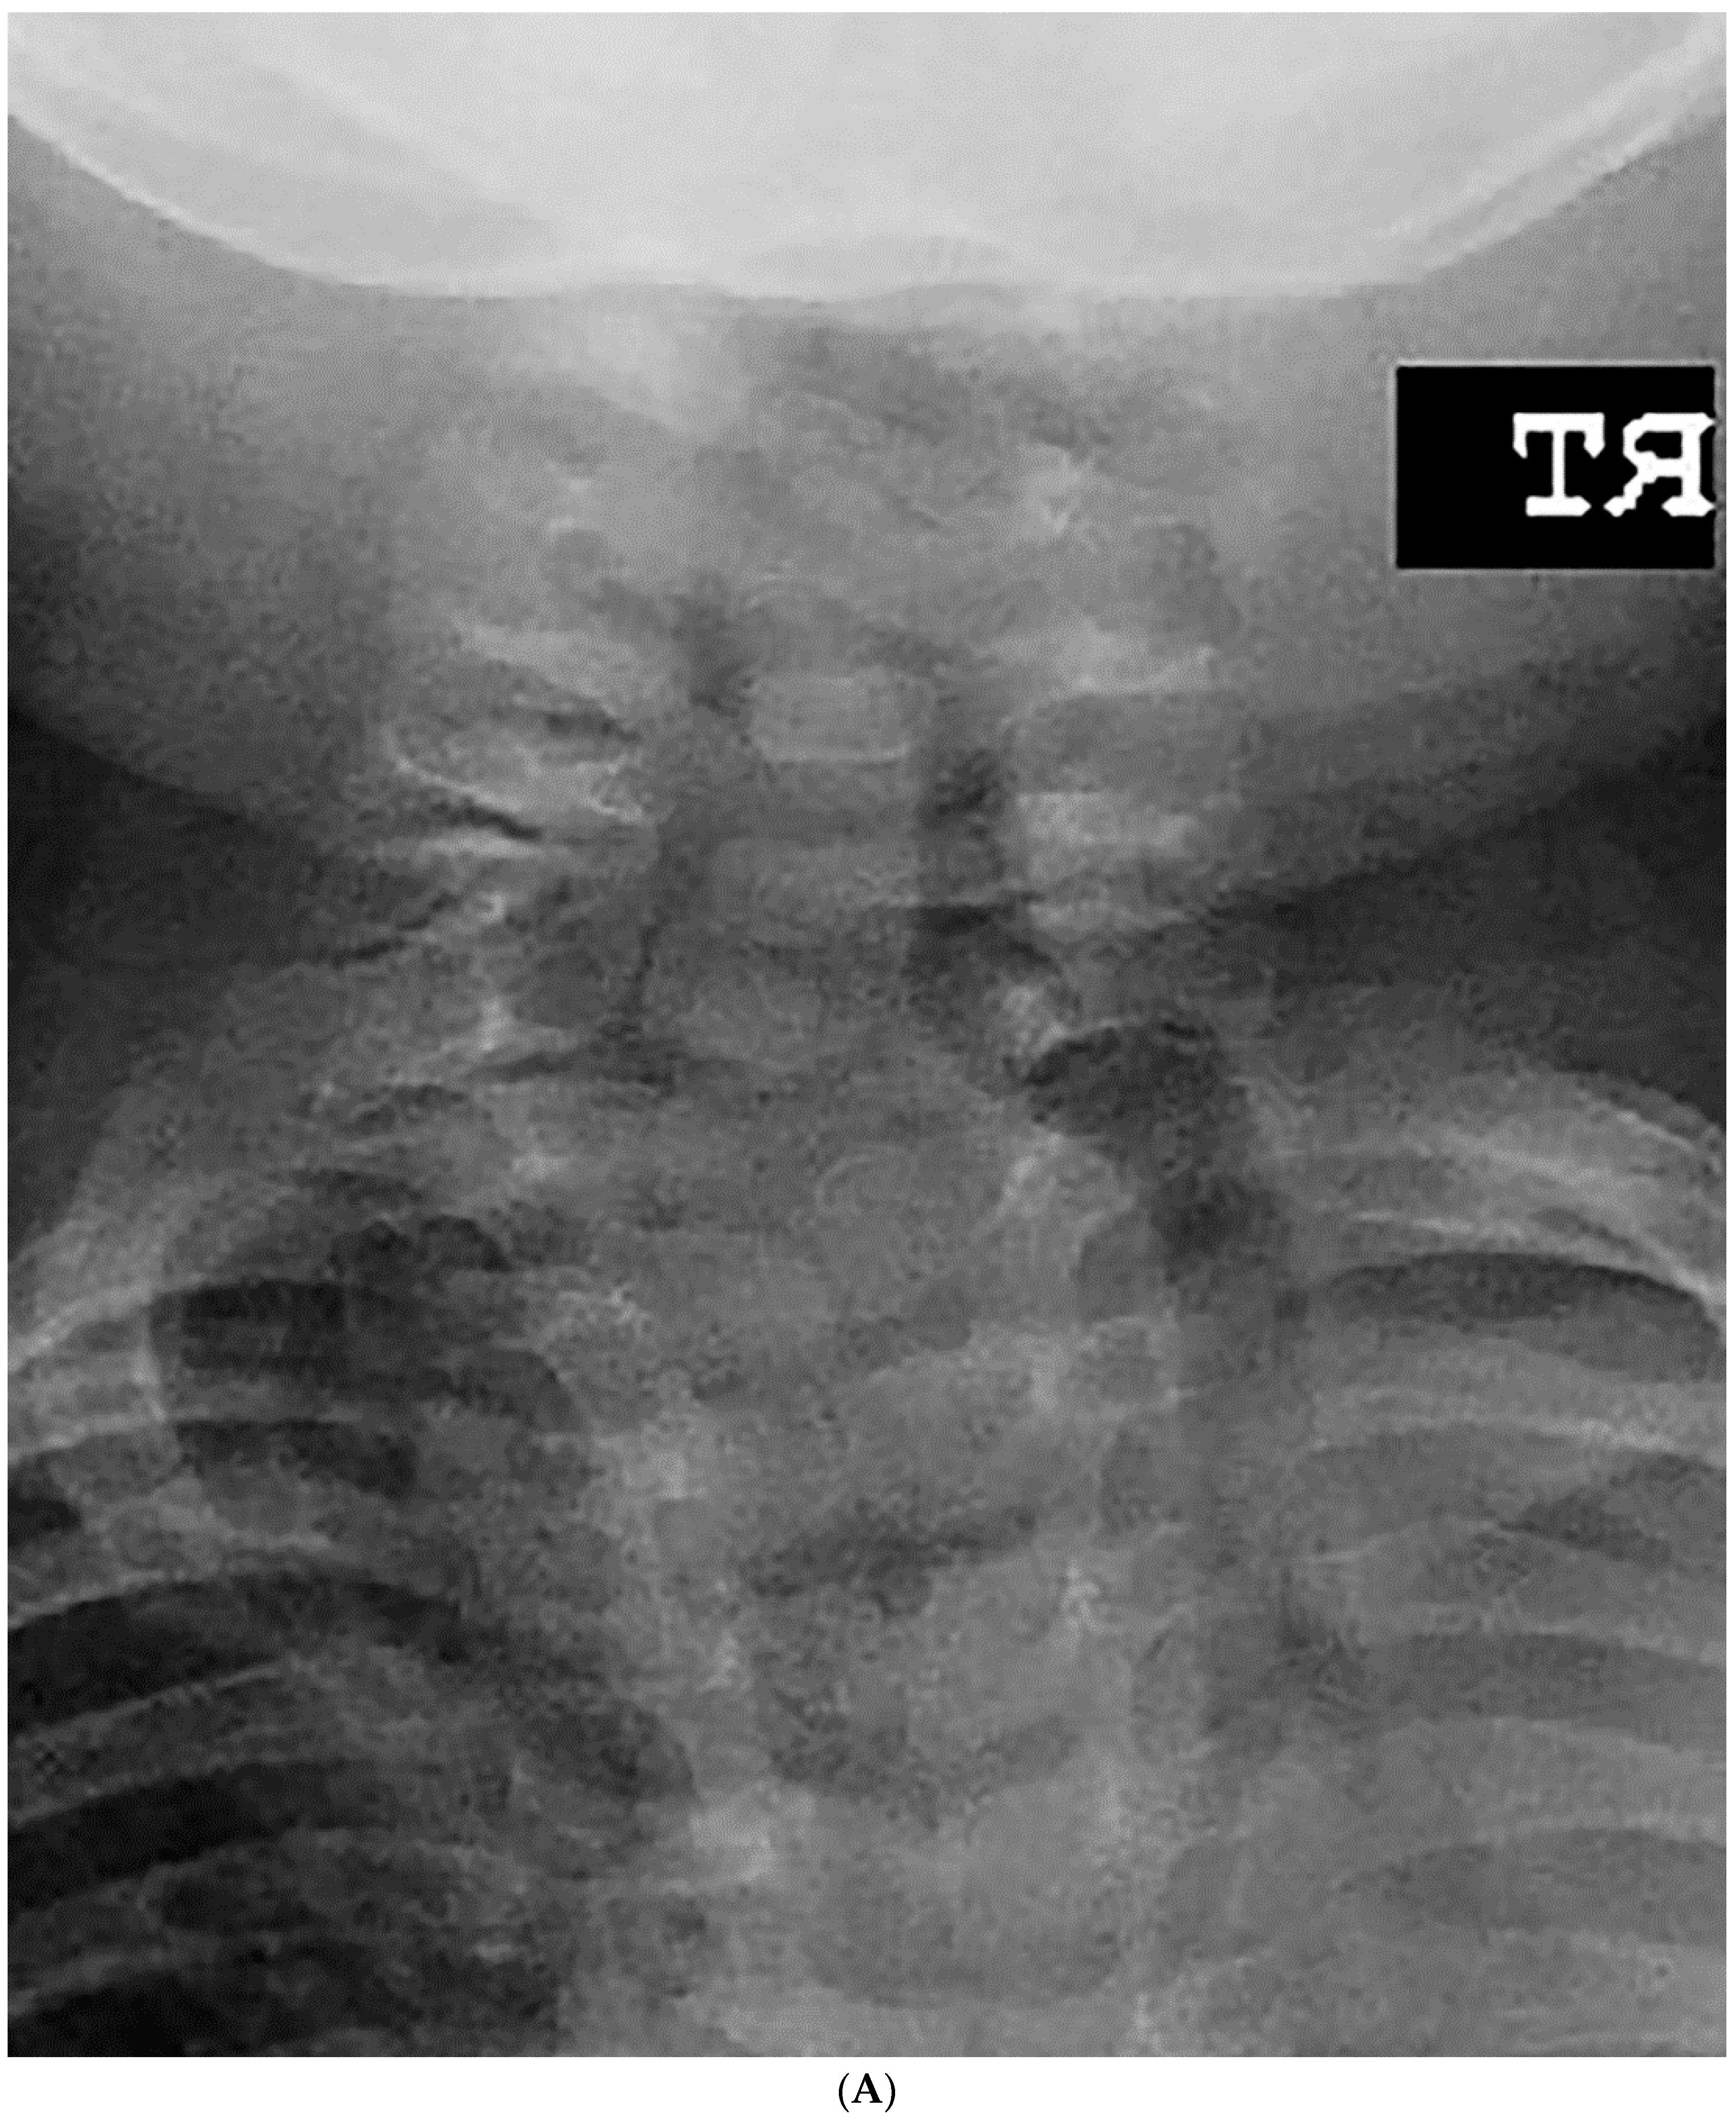

Figure 1.

(A–C). A 10-year-old boy diagnosed with congenital cervical scoliosis (CCS) initially (A). This patient has C3 and C7 hemivertebrae with progression of cervical and compensatory curves (B,C).